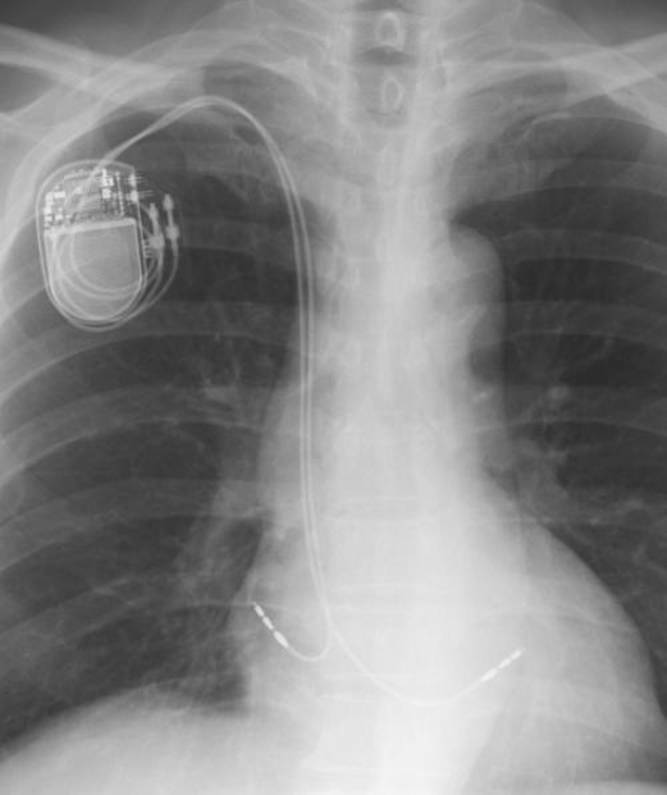

点滴をやめ飲み薬にする。胸部の写真を撮って貰う。

20120210114501

20120210114502

20120210114601

20120210114602

201202132330(右胸PM植込み後)

201202132331 (左胸PM抜去後)